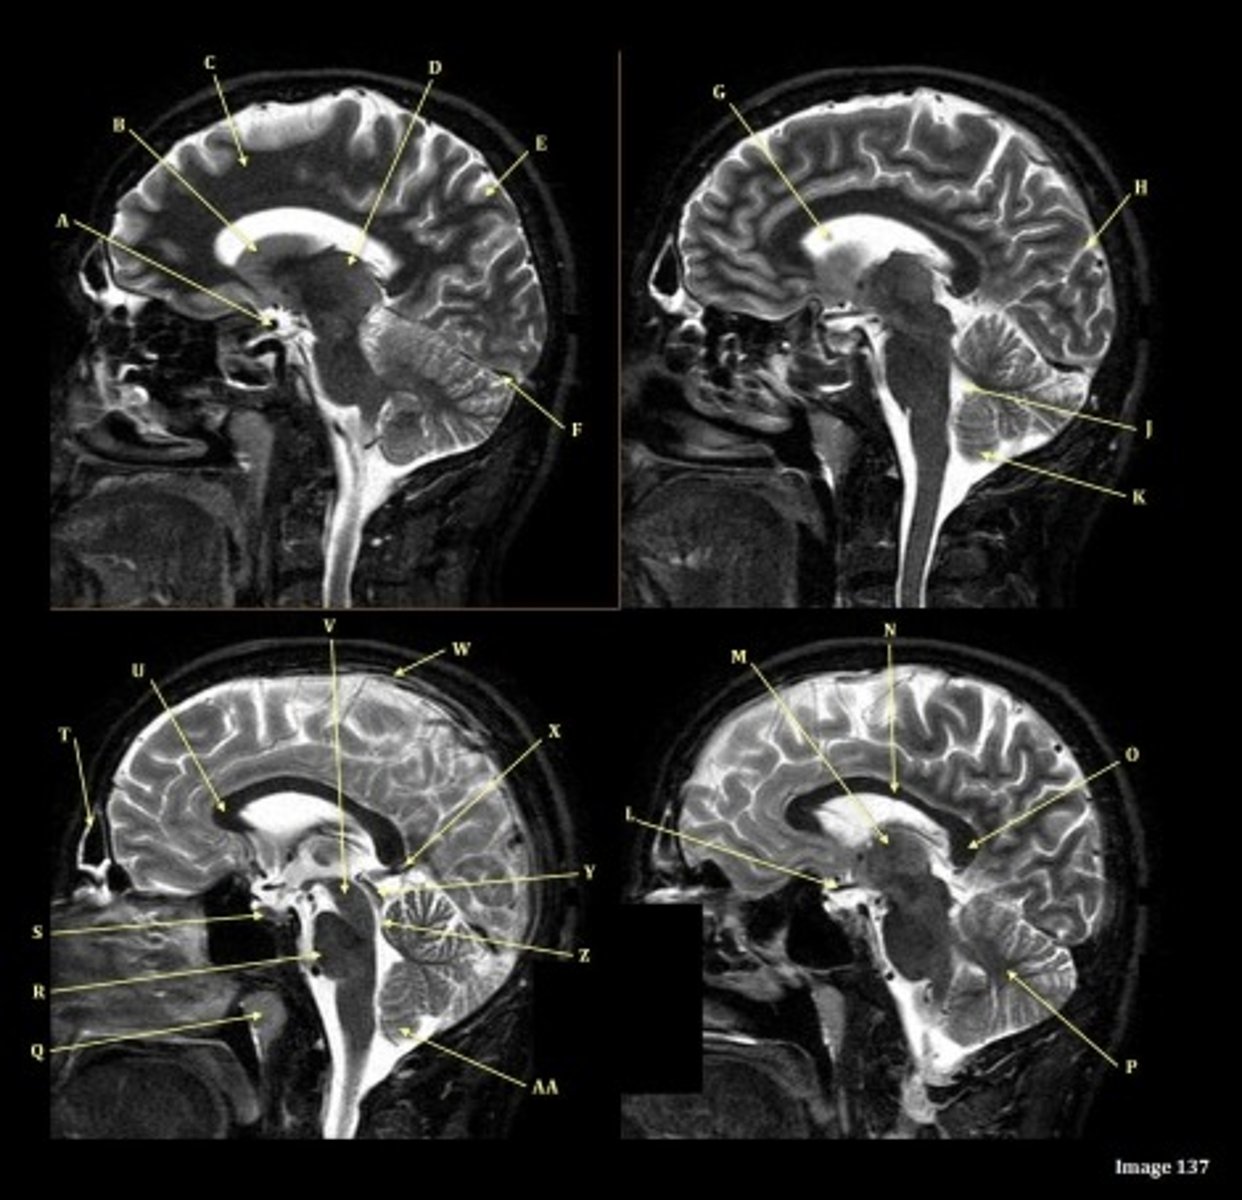

What type of sequence?

T2 FLAIR; Sagittal

A FLAIR (Fluid Attenuated Inversion Recovery) sequence is utilized to suppress signal from cerebrospinal fluid (CSF).

A

lateral ventricle

B

corpus callosum

C

thalamus

D- separates what

tentorium cerebelli- cerebrum (occipital and temporal lobes) from brainstem and cerebellum

E

fourth ventricle

F

medulla oblongata

caudate nucleus

third ventricle

D

lentiform nucleus

frontal sinus

V

Cerebral peduncle

W

superior sagittal sinus

X

vein of galen

Y

Inferior colliculus of midbrain,

just inferior to pineal gland / superior to the cerebral aqueduct

Letter N in Image 137 is pointing to what type of tissue?

White matter

The corpus callosum is the only white matter tissue structure found in the midline sagittal slice of the brain.